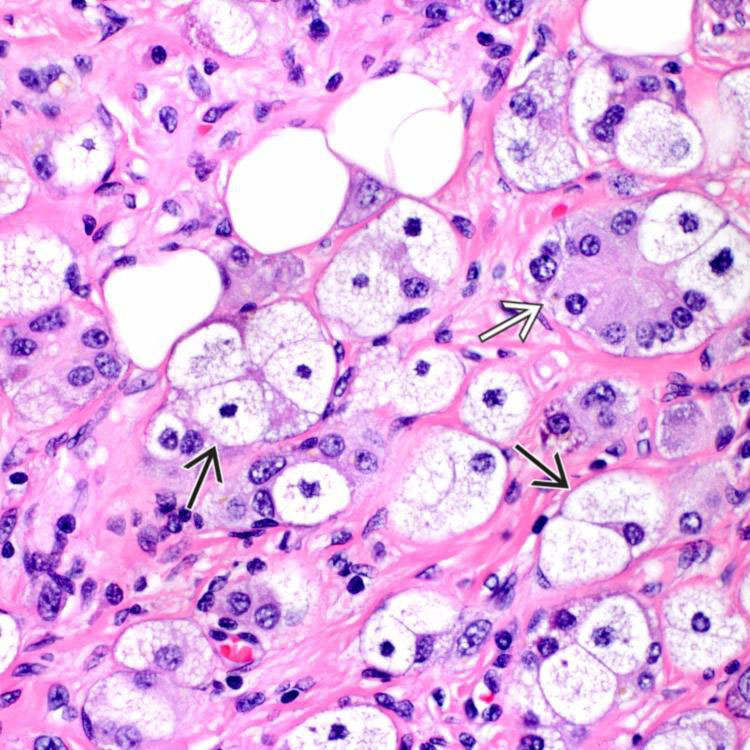

From www.pathologyoutlines.com

Pathology Outlines Clear cell pancreatic endocrine tumor Foamy Cells Tumor Foam cells play a vital role in the initiation and development of atherosclerosis. Pdacs are a heterogeneous group of malignant pancreatic epithelial neoplasms. This review aims to summarize the novel insights into the origins,. Chronic inflammation in many infectious and metabolic diseases, and some cancers, is accompanied by the presence of foam. Here, we mainly described the unusual histological variants. Foamy Cells Tumor.